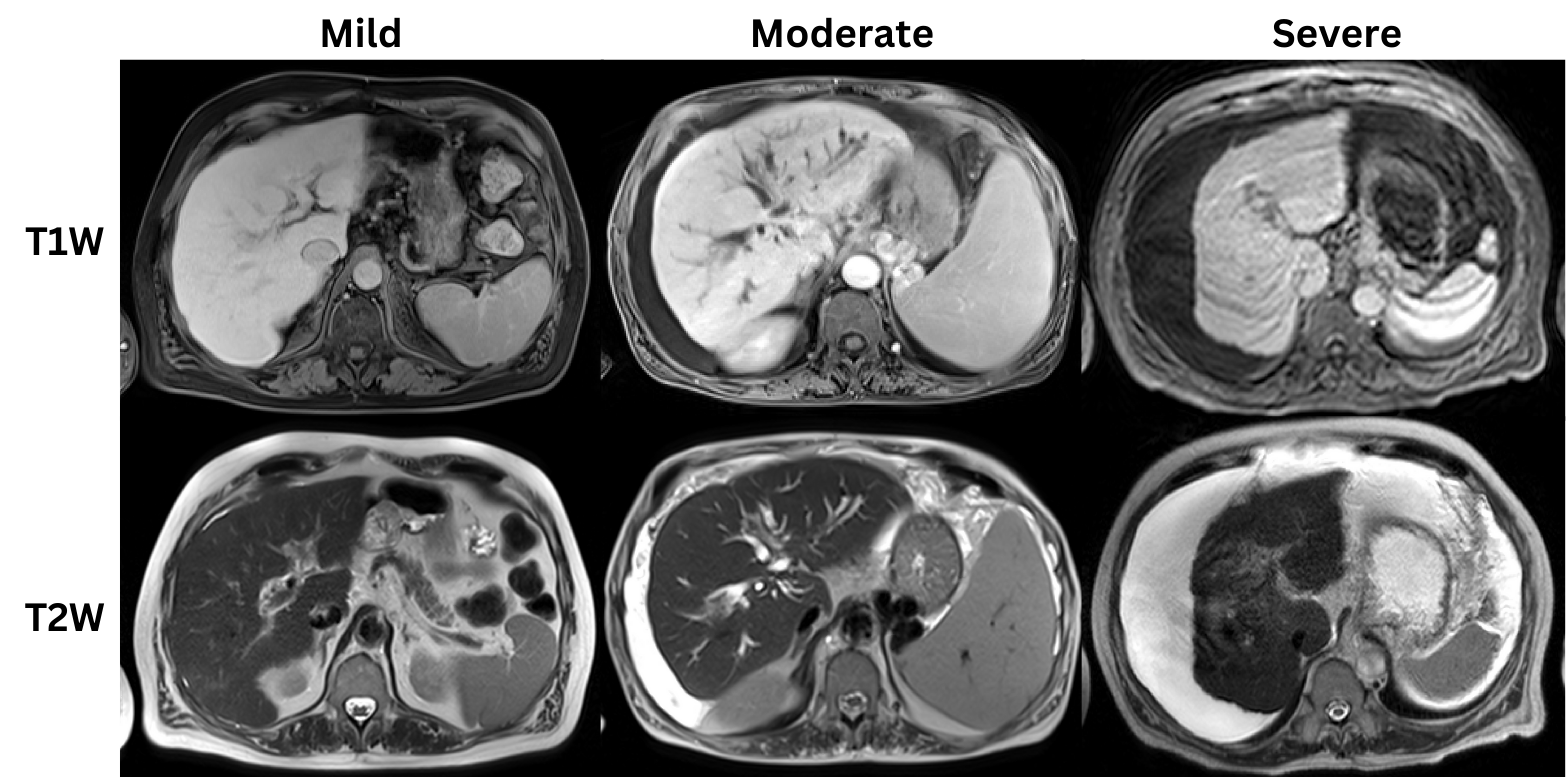

Dataset: Our framework addresses the challenging task of liver cirrhosis stage estimation through a comprehensive deep learning approach. The CirrMRI600+ dataset forms the foundation of our work, comprising 628 high-resolution abdominal MRI scans from 339 patients diagnosed with liver cirrhosis. This diverse dataset includes 310 T1W and 318 T2W scans, providing rich multi-sequence information for stage classification. We employ an 8:1:1 split ratio, allocating 234 samples for training, 29 for validation, and 28 for testing, ensuring robust evaluation of our methods. Fig.1 presents examples of T1W and T2W MRI scans for mild, moderate, and severe cirrhotic cases.